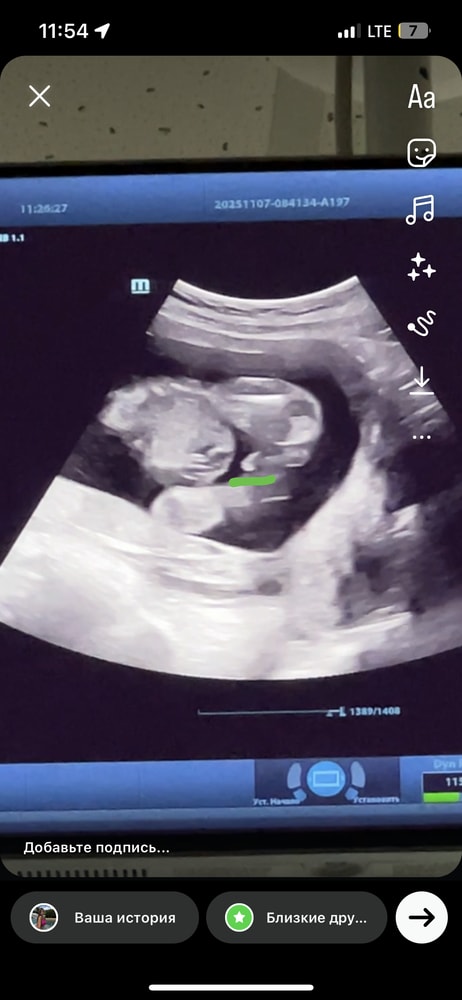

По первому фото я вообще понять ничего не могу . А вот тут оно самое ?😂 записалась еще на одно узи , через неделю. Уже не могу ждать ) или уже правда кровь сдать Изображение

Евгения, 😌 где? Я тоже хочу ее увидеть 😅 вот это тогда что 🙈 Изображение

Изображение

Маша, ну у вас по-моему это не пуповина, с первым сыном у нас писюн такой же был на экране, а в эту беременность вот так и то что я обвела зеленым меня смущает ибо узистка утверждала, что то, что обведено красным это писюн, но по-моему это как раз пуповина в срезе😅 Изображение Изображение Изображение